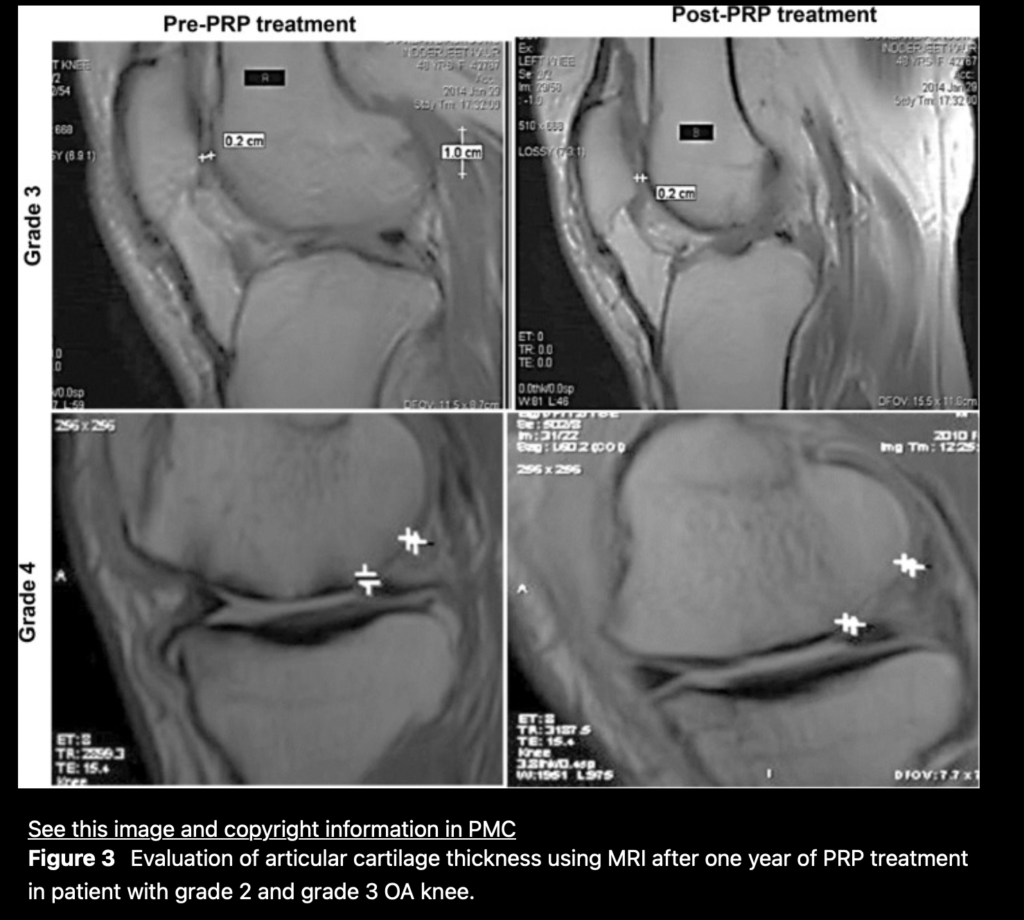

Again, not a method that is optimal when you are investing in a proven procedure to heal your body. There is substantial literature showing the beneficial results of PRP treatment. A substantial improvement in osteoarthritis has been shown, actually thickening the articular cartilage in the knees. This is quite incredible due to the fact that this area of cartilage is challenging to heal, seeing that it is avascular and receives nutrients via diffusion of the synovial fluid.

PRP has shown to thicken the cartilage of the knee, preventing further degradation and potent for bone-on-bone in the joint.